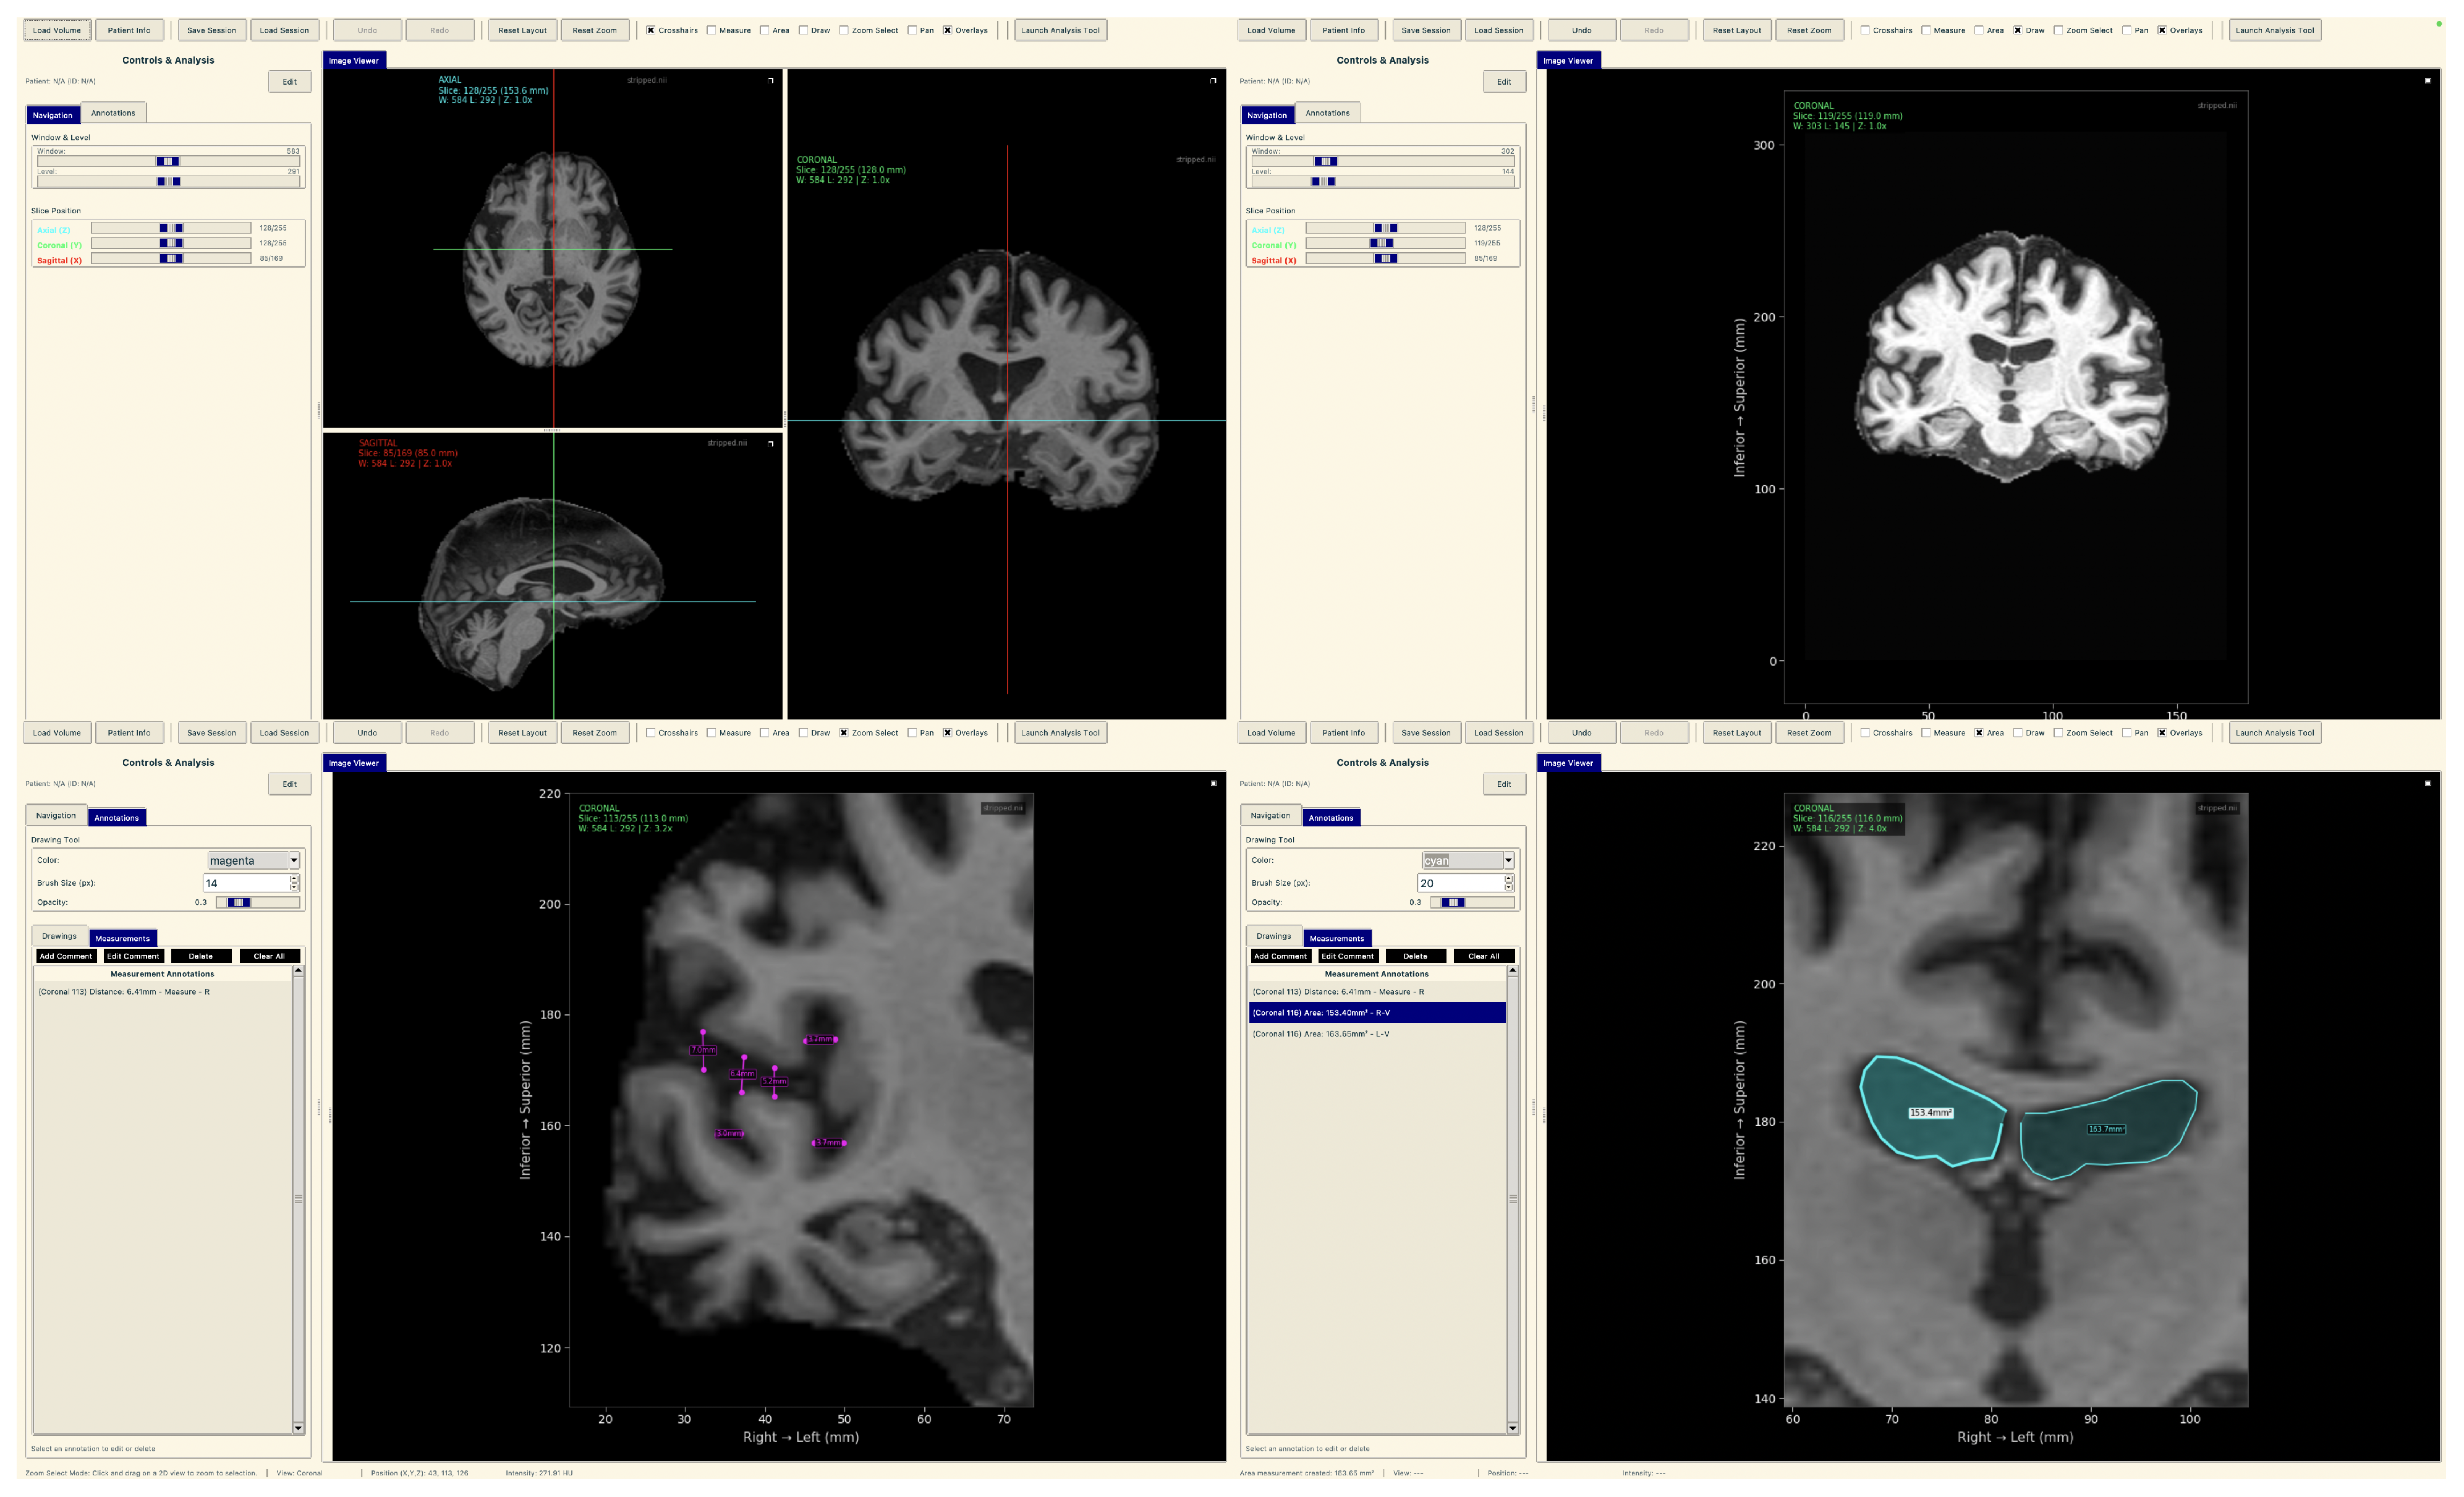

The raw 3D neuroimages underwent a rigorous, multi-stage preprocessing pipeline which is illustrated in Figure 3. To ensure our analysis focused purely on neuroanatomical structures, we first performed automated skull stripping using SynthStrip (FreeSurfer v8.0.0). This deep learning-based tool was specifically chosen because it operates without requiring spatial registration to a standardized brain template [56]. This registration-free approach is crucial as it preserves the native anatomical geometry of each subject’s brain and avoids the introduction of interpolation artifacts that can arise from spatial normalization [57]. Following skull stripping, each brain volume was reoriented to the RAS (Right–Anterior–Superior) canonical space to harmonize the data across the multi-site cohort.

Figure 3.

The end-to-end data preparation pipeline.

From these aligned volumes, we extracted 2D slices exclusively from the coronal plane, providing a cross-sectional perspective along the ventral–dorsal axis. This view was deliberately selected as it offers the most direct and clinically relevant perspective for assessing the morphology of the hippocampus and surrounding medial temporal lobes, which are primary sites of early AD pathology [58,59]. This pipeline yielded a final dataset of 3000 2D image slices, 1000 per category. For each subject, we systematically extracted ~30 consecutive coronal slices centered around the volumetric midpoint of the coronal axis (slice range: , where represents the center index), specifically targeting the medial temporal region containing the hippocampus and surrounding structures critical for early AD pathology. We computed brain tissue bounding boxes using a fifth percentile intensity threshold, removed small objects (minimum size 256 pixels), applied binary closing (disk radius 5 pixels) to reduce noise, and excluded slices with zero intensity sums. This protocol extracted up to 30 slices per subject from the medial temporal region, yielding 1000 high-quality slices per diagnostic category across 102 subjects with consistent anatomical coverage. Slices were extracted as consecutive 2D arrays from the coronal plane without skipping frames, ensuring continuous anatomical coverage of hippocampal and periventricular structures throughout the medial temporal lobe region. To standardize the spatial dimensions for model input, we implemented an aspect ratio-preserving method where each slice was tightly cropped to the brain’s bounding box before being resized to fit within a 224 × 224 canvas, with zero-padding used to maintain anatomical proportions. Finally, each slice was intensity-scaled to the 0–255 range and stored in PNG format to simplify data handling and enhance accessibility.